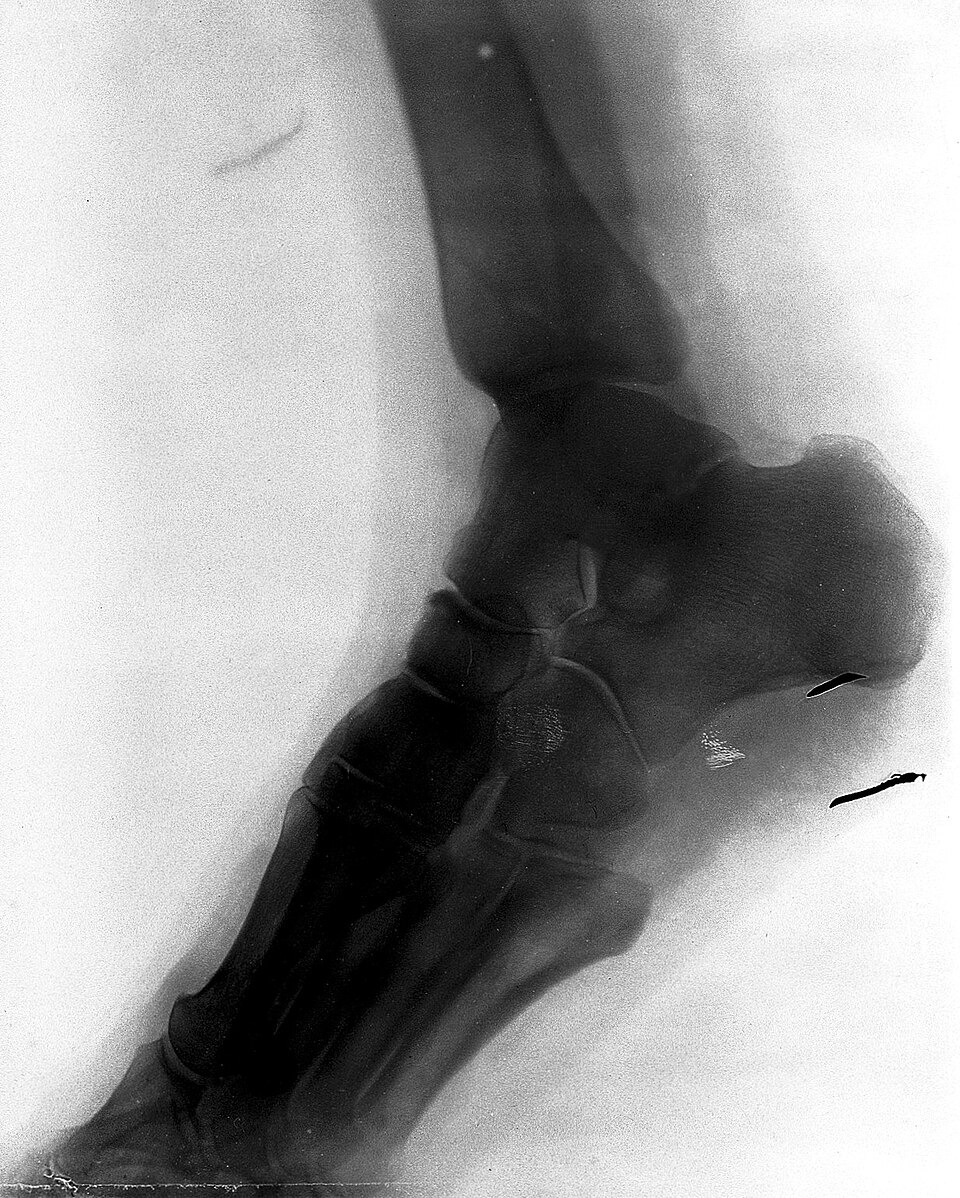

Ankle and foot phantom with talus, calcaneus, tarsal bones, Achilles tendon, and lateral ligaments